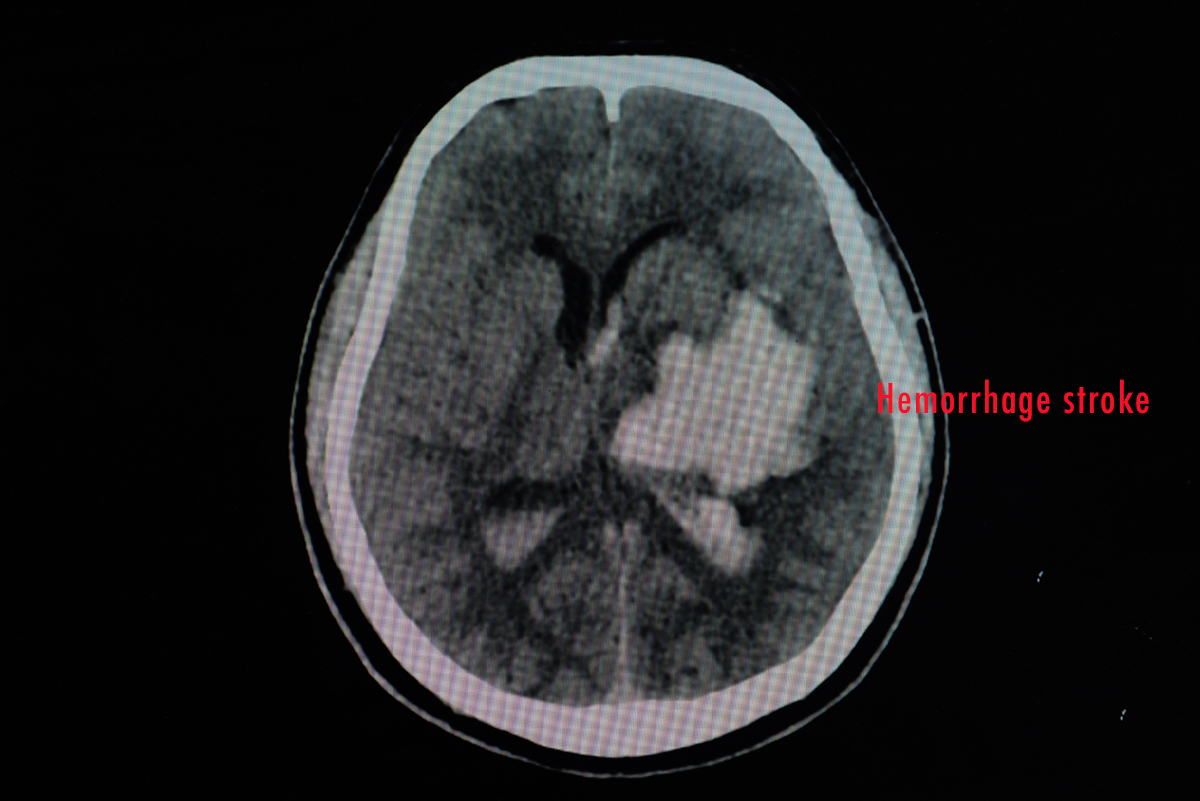

脳卒中は、脳梗塞(のうこうそく)、くも膜下出血、脳出血の3つに分けられます。

脳梗塞とは、脳の動脈が詰まって血液の流れが悪くなり、脳がダメージを受ける病態です。

そして脳出血とは、脳の血管が破れて血液が漏れ出る病態です。

昔から脳溢血(のういっけつ)という言葉がありますが、それは「血が溢(あふ)れる」、つまり脳出血と同義だとご理解ください。